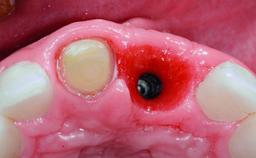

A healthy 37-year-old female patient was referred for a consultation on the replacement of missing tooth 21 with an implant-supported restoration. She stated that several years previously the tooth had been traumatically avulsed following a motor vehicle accident. The tooth was replaced with a three-unit fixed partial denture (FPD) immediately afterwards. Over time, she became disillusioned with the FPD and looked for a different option, including orthodontic therapy. She presented still in her orthodontic appliances, with the pontic sectioned free from the FPD but attached to the archwire. Her orthodontist felt that orthodontic treatment had been successfully completed, but nevertheless referred her before removing the appliances in case adjustments were necessary.

| Bone Augmentation | Horizontal|Simultaneous |

| Bone Volume | Deficient horizontally, allowing simultaneous augumentation |